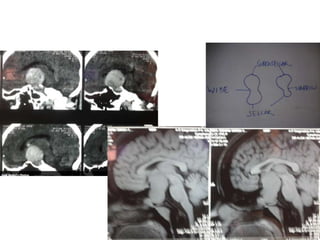

3rd ventricle

3rd ventricle entered through

1. Supra optic chiasmic route – by Lamina terminalis

2. Infra optic chiasmic route – by Tuber cinerereum

Infra optic chiasmic route – by

Tuber cinerereum

3rd ventricle entry by - Supra optic chiasmic route – by

Lamina terminalis

FM – Foramen of Monro